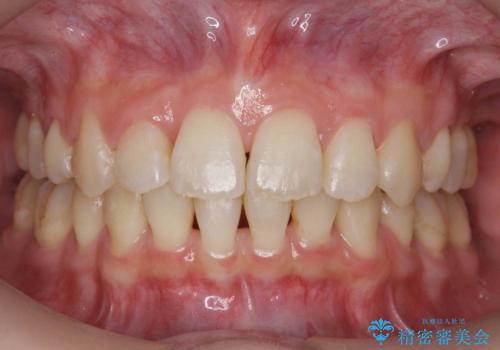

- 20代女性

- 虫歯治療を担当した先生からの紹介。

左上の小臼歯が込み合っており、虫歯治療が厳しい状態でした。

矯正治療をおすすめし、ちょうど虫歯がひどい歯は抜歯して前歯を下げました。